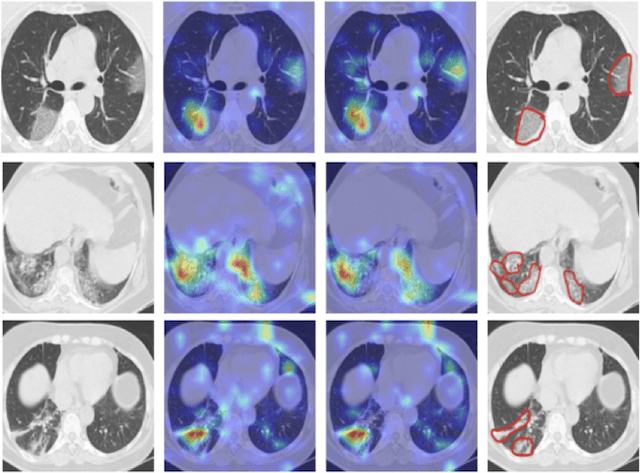

Abstract:The novel corona-virus disease (COVID-19) pandemic has caused a major outbreak in more than 200 countries around the world, leading to a severe impact on the health and life of many people globally. As of Aug 25th of 2020, more than 20 million people are infected, and more than 800,000 death are reported. Computed Tomography (CT) images can be used as a as an alternative to the time-consuming "reverse transcription polymerase chain reaction (RT-PCR)" test, to detect COVID-19. In this work we developed a deep learning framework to predict COVID-19 from CT images. We propose to use an attentional convolution network, which can focus on the infected areas of chest, enabling it to perform a more accurate prediction. We trained our model on a dataset of more than 2000 CT images, and report its performance in terms of various popular metrics, such as sensitivity, specificity, area under the curve, and also precision-recall curve, and achieve very promising results. We also provide a visualization of the attention maps of the model for several test images, and show that our model is attending to the infected regions as intended. In addition to developing a machine learning modeling framework, we also provide the manual annotation of the potentionally infected regions of chest, with the help of a board-certified radiologist, and make that publicly available for other researchers.